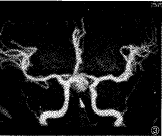

图6~8 患者,女,46岁。既往有蛛网膜下腔出血史。

图6:DSA示哑铃 形前交通动脉动脉瘤。

图7:MIP像示右侧大脑前动脉A1段先天缺如,右侧大脑前动脉通过 瘤状扩张的前交通动脉供血。

图8:MPR像显示前交通动脉呈哑铃形扩张与双侧大脑前动脉的 关系较DSA及MIP像更清楚

值得指出的是,MRA以往被理解为主要是评价MIP像。MIP像是采用最大信号投影技术处理原 始图像,仅代表最高信号的象素完全投影而使血管成像。但是,这种方法的限度变得日益突 出。目前强调应用MRA进行脑血管疾病的诊断要对MRA的原始像、SE像、MPR像和MIP像进行综 合复习观察。在一项研究中,当原始像、SE像和MIP像联合观察时,3D TOF MRA诊断颅内动 脉瘤的敏感性从67%提高到86%[7]。复习原始像和SE像也有助于准确判断与动脉血 流无关的高信号区域,如垂体后叶和副鼻窦含蛋白潴留囊肿,可能在MIP像中类似动脉瘤, 但其在原始像和SE像中有其特殊定位以利确诊[8]。原始像、仅含动脉瘤和载瘤血 管的靶MIP像、MPR像以及SE像的综合观察可减少血管重叠,很好显示动脉瘤的准确结构(图6 ~8)。最近Tae-sub Chung等[6]报道,共同应用MRA的MIP像和MPR像成功显示全部 39个(100%)动脉瘤的颈部及颈部和载瘤血管的关系;而仅用MIP像的MRA成功显示27个(69%) ,DSA成功显示32个(82%)。在评价动脉瘤颈部和载瘤血管的关系方面,联合应用MRA的MIP像 和MPR像远超过单用MRA的MIP像或DSA。本组的结果也说明了这一点。